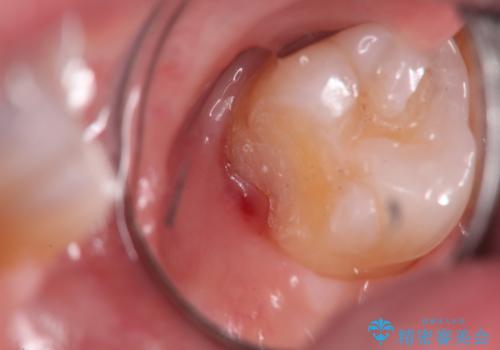

- 検査の結果、左上の一番奥の歯のさらに奥の面の深い位置に虫歯が潜んでいることを確認しました。

外から見えない位置であるため、セラミックよりも精度を上げることができるゴールド(PGAインレー)で修復していきます。

昔親知らずが埋まっていた場所にできてしまった虫歯であるためかなり深い位置に潜り込むような虫歯でした。

このような虫歯でも丁寧に処置することで問題なく適合の良いインレーを入れることができます。